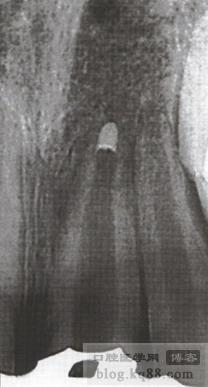

5、繼續(xù)輸送,直至MTA達(dá)到5mm以上然后壓實壓平,拍片確認(rèn)后,MTA上放一濕棉球以便于MTA更好的凝固,然后冠部開口雙層嚴(yán)密封閉

6、第二天復(fù)診,檢查MTA已完全凝固且封閉良好后,根管上段用牙膠封閉至秞牙骨質(zhì)下方 ,如做樁留出空間